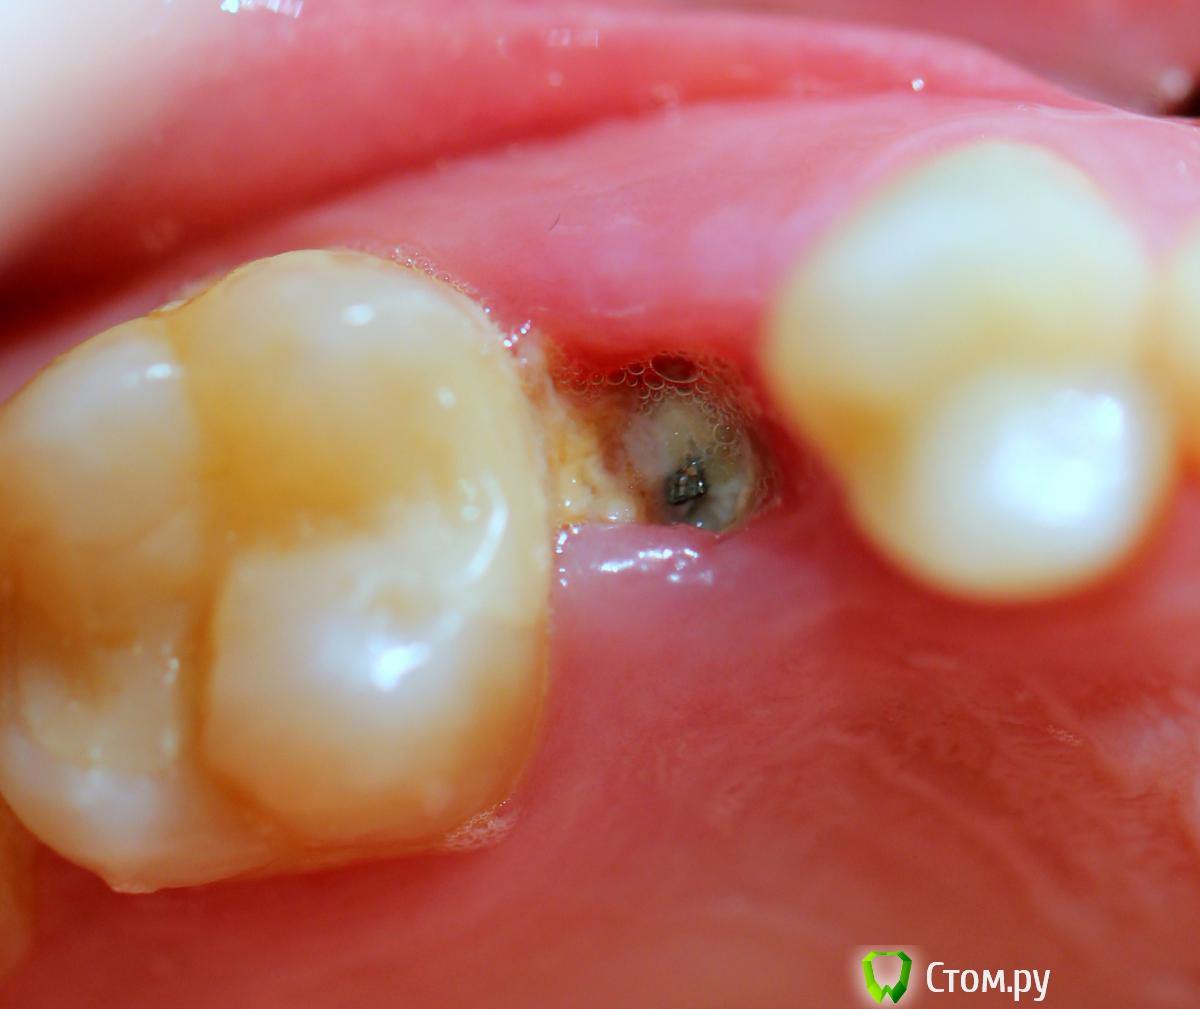

Andex Опубликовано 6 июля, 2014 Поделиться Опубликовано 6 июля, 2014 Всем привет! Вдохновленный великолепными кейсами докторов с форума, выкладываю свой случай. Коментарии и критика(особенно) приветствуются! Пациент обратился с переломом корня Я решил пойти по простому пути, тк мукогингивальными трансплантатами не владею в должном качестве - просто сошлифовал корень на 1,5 мм ниже прикрепления, и подождал 2 недели - знаю, что маловато, но руки чесались сделать операцию. Вид через 2 недели Удаляем корень и ставим имплант Устанавливаем заглушку Мобилизируем лоскут с неба и ушиваемся, нитка - моносин 5.0 Виновник торжества - слегка в стиле гиперреализма Снимки до и после имплантации - визиограф не информативен в полной мере - вживую имплант заглублен мах на 2 мм 4 Ссылка на комментарий

Andex Опубликовано 6 июля, 2014 Автор Поделиться Опубликовано 6 июля, 2014 и кроме мезио-достального расстояниявинт - семадоз r-line? (3.25) что с вестибулярной кортикальной пластинкой? (как правило, при таких переломах она отсутствует) Винт - osstem d4.5 - L10.0.Вестибулярно кортикальной нет примерно на 2 мм в области шейки зуба, далее апикальнее она впорядке, поэтому ришлось заглублять на 2 мм(фотки что то перестали загружаться) - и получилось, что винт встал вровень с кортикальной весибулярно и на 2мм субкрестально с небной стороны.- насколько это критично? Сошлифовать 2 небных мм рука не поднялась Ссылка на комментарий